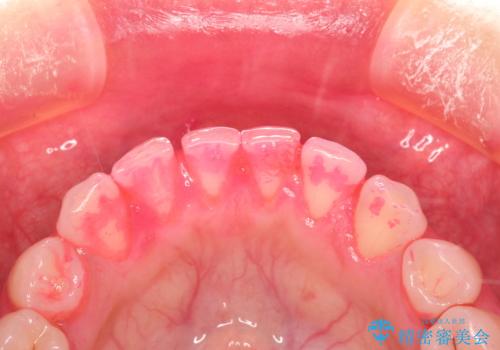

終了時

かなり久しぶりの歯科医院との事で、全体的に古くからの歯垢・歯石が多く付着していたため、自費クリーニング(PMTC)60分コース・歯周ポケット検査(保険適応)を行いました。

磨き残しが放置されると、そこで病原菌が繁殖し始めます。よって歯肉に炎症が生じ、歯周病の原因になることがあります。

定期的に、歯周病検査や専門的なクリーニングをすることで、早期発見につながります。